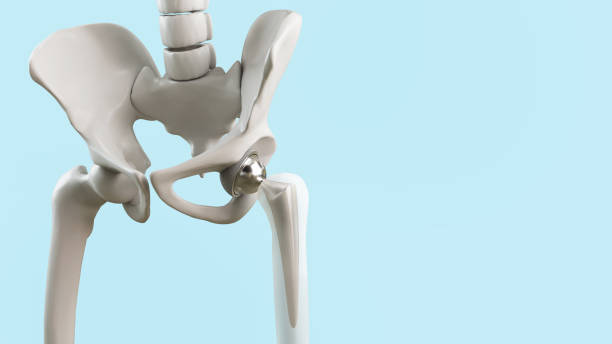

고관절 통증의 일반적인 원인 중 하나는 허리디스크입니다. 허리디스크는 허리 부위의 디스크에 문제가 생겨 발생하며, 이로 인해 통증을 겪게 됩니다. 하지만 모든 고관절 통증이 허리디스크로 연결되지는 않습니다. 고관절 주변에도 다양한 원인이 숨어 있을 수 있습니다.

고관절 통증은 종종 단일 원인뿐만 아니라 복합적인 문제에서 비롯됩니다. 이것이 진단과 치료를 어렵게 만들 수 있습니다. 예를 들어, 허리디스크와 함께 관절 주위의 염증, 근육 문제, 혹은 다른 구조적 문제가 동시에 발생할 수 있습니다.